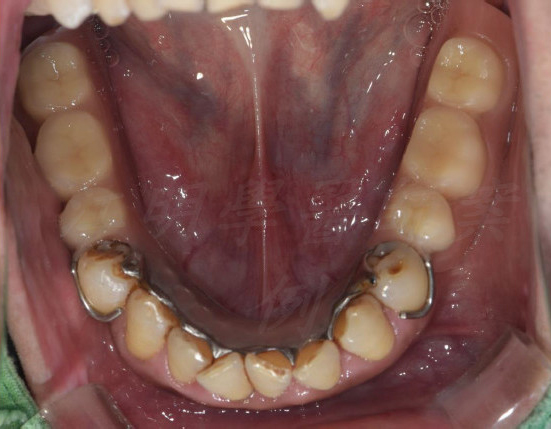

活動式假牙案例

牙齒狀況改善

治療前

治療後

這些照片展示了您的牙齒在術後得到顯著改善,排列更加整齊、美觀,並達到理想的咬合狀態。

也能增強口腔健康。